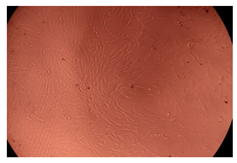

The results of the cytotoxicity assay, given in Figure 5, indicate that the tested PMs at all three established concentrations (10, 50, and 100 µg/mL) did not show cytotoxic effects on fibroblast cells at either 24 or 48 h after incubation. The percentages of cell viability were high, over 90%, in cells that were exposed to a concentration of 10 µg/mL for 24 h for all tested materials. Even at 48 h after incubation, the percentage of cell viability was as high as 90.4% in cells exposed to a concentration of 10 µg/mL for the Cop B sample. For both drug-loaded PMs, the cell viability decreased slightly at all tested concentrations. It also appears that the Dorzolamide-loaded PMs have slightly lower cell viability as compared to IMC-loaded PMs. Micrographs of the fibroblast cells after incubation times of 24 and 48 h are provided in Table 2.

Table 2.

Micrographs of fibroblast cells after 24 and 48 h incubation times, respectively.

As the cell viability values are all over 80%, the results indicate that the PMs, at the established concentrations, can be used successfully for in vivo biomedical applications.